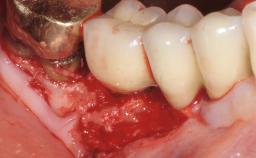

Peri-Implant Mucositis Associated with Misfit of a Cemented Restoration

A 37-year-old male patient was referred to the Department of Periodontology at the University of Bern, Switzerland, by a private dentist. Tooth 21 had been lost due to trauma and had been replaced with an implant and a cemented single crown. The tapered-effect tissue-level implant had a diameter of 4.1 mm, a length of 12 mm, and a sandblasted and acid-etched (SLA) surface (Straumann Dental lmplant System; Institut Straumann AG, Basel, Switzerland). The metal-ceramic crown had been cemented permanently, leaving a submucosal gap between the implant shoulder and the crown margin. Absence of marginal bone loss apical to the polished transmucosal neck of the implant could be observed .